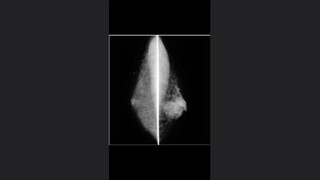

Nódulos